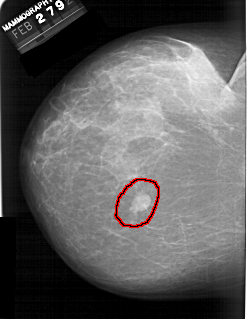

A_1389_1.LEFT_MLO

LEFT_MLO LINES 6361 PIXELS_PER_LINE 5191 BITS_PER_PIXEL 12 RESOLUTION 43.5 OVERLAY

FILE: A_1389_1.LEFT_MLO.OVERLAY

TOTAL_ABNORMALITIES 1

ABNORMALITY 1

LESION_TYPE MASS SHAPE LOBULATED MARGINS CIRCUMSCRIBED

ASSESSMENT 4

SUBTLETY 5

PATHOLOGY BENIGN

TOTAL_OUTLINES 1

BOUNDARY